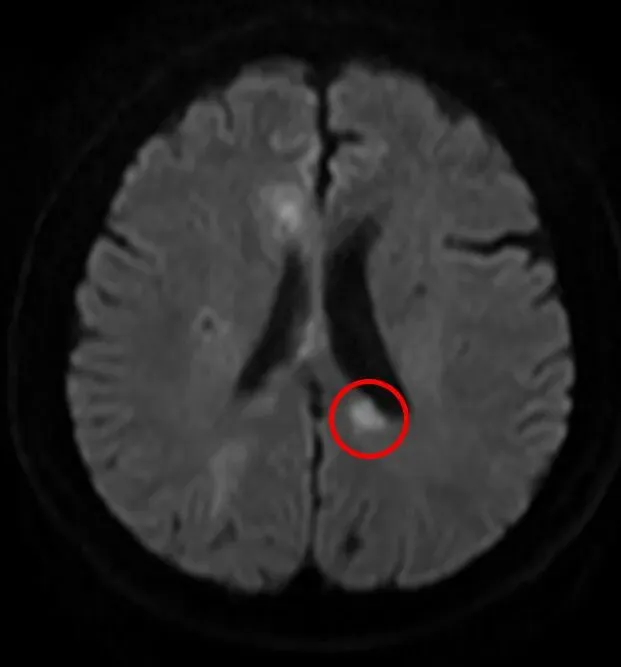

激素治疗前

激素治疗后,脑内动脉强化范围减小、强化程度减低,患者症状显著改善。